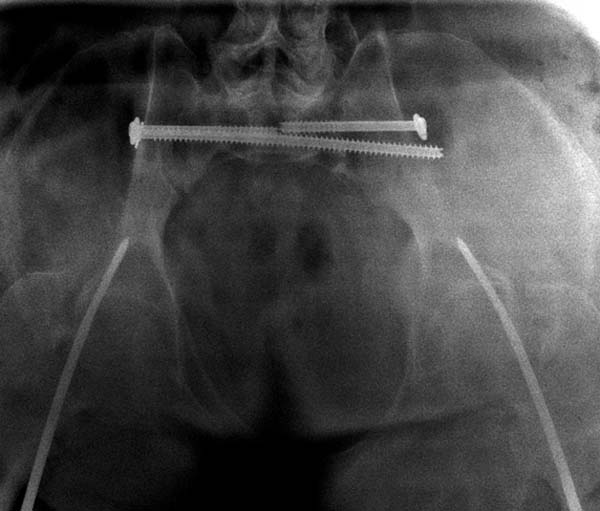

Двухстороннее повреждение крестца и травматическая ампутация бедра, где

неопытной бригадой дежурантов установлен верхний наружный фиксатор для

стабилизации. На третий день ревизия на более стабильный, и

окончательная фиксация. Первые снимки после стабилизации таза, и другие,

где показаны (параллельные) правильная установка на AIIS т.е на месте

прикрепления прямой мышцы бедра. Ампутация закончена костно пластическим

методом.